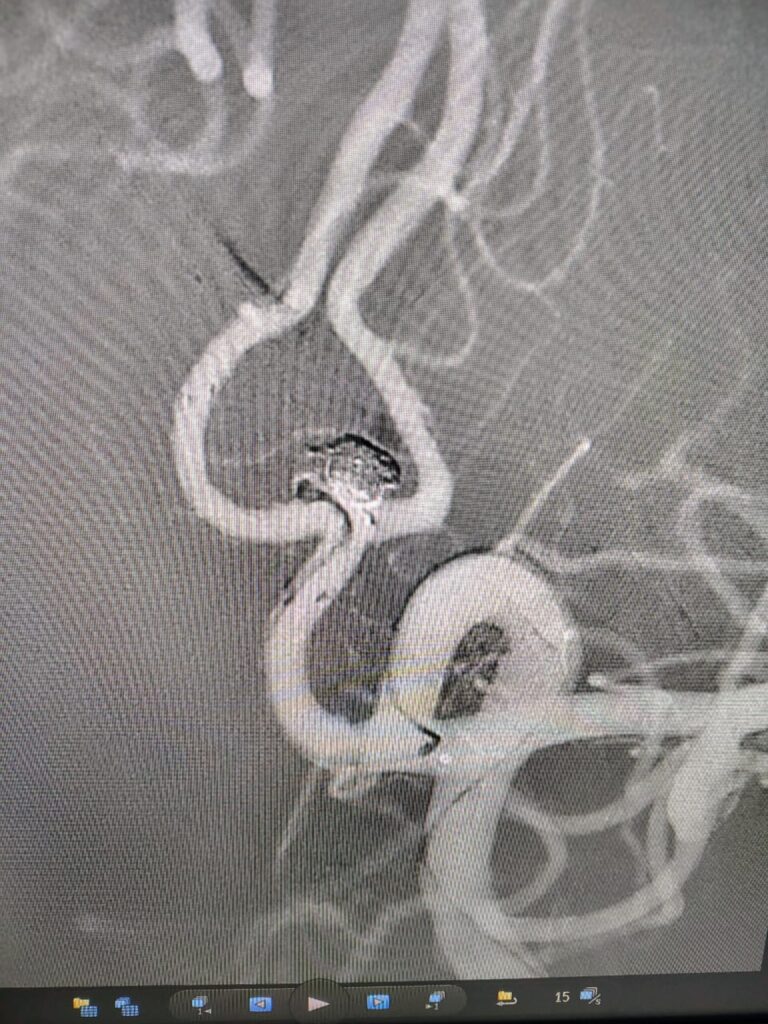

Ruptured Brain aneurysm (left ICA communicating segment wideneck aneurysm) treated with Stent Assisted Coiling.

aneurysm cannulated with microcatheter and microwire

Coiling in live case

after complete coiling and stenting

final result complete coiling and Stenting of brain aneurysm